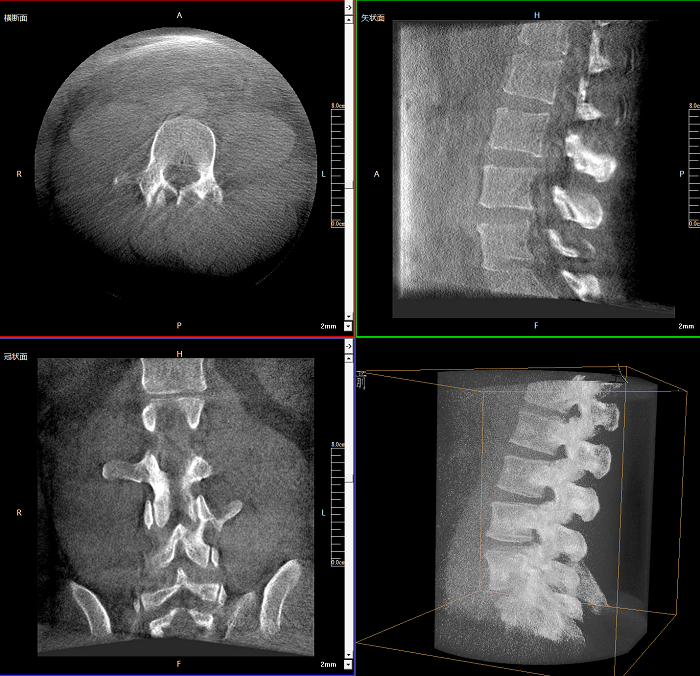

三維成像 全面觀察

任意視角、任意切面觀察

術(shù)中實(shí)時(shí)生成橫斷面、矢狀面、冠狀面及三維影像,可在任意切面、任意角度評估植入物和解剖結(jié)構(gòu)的相對位置。

Clinical picture

臨床圖片